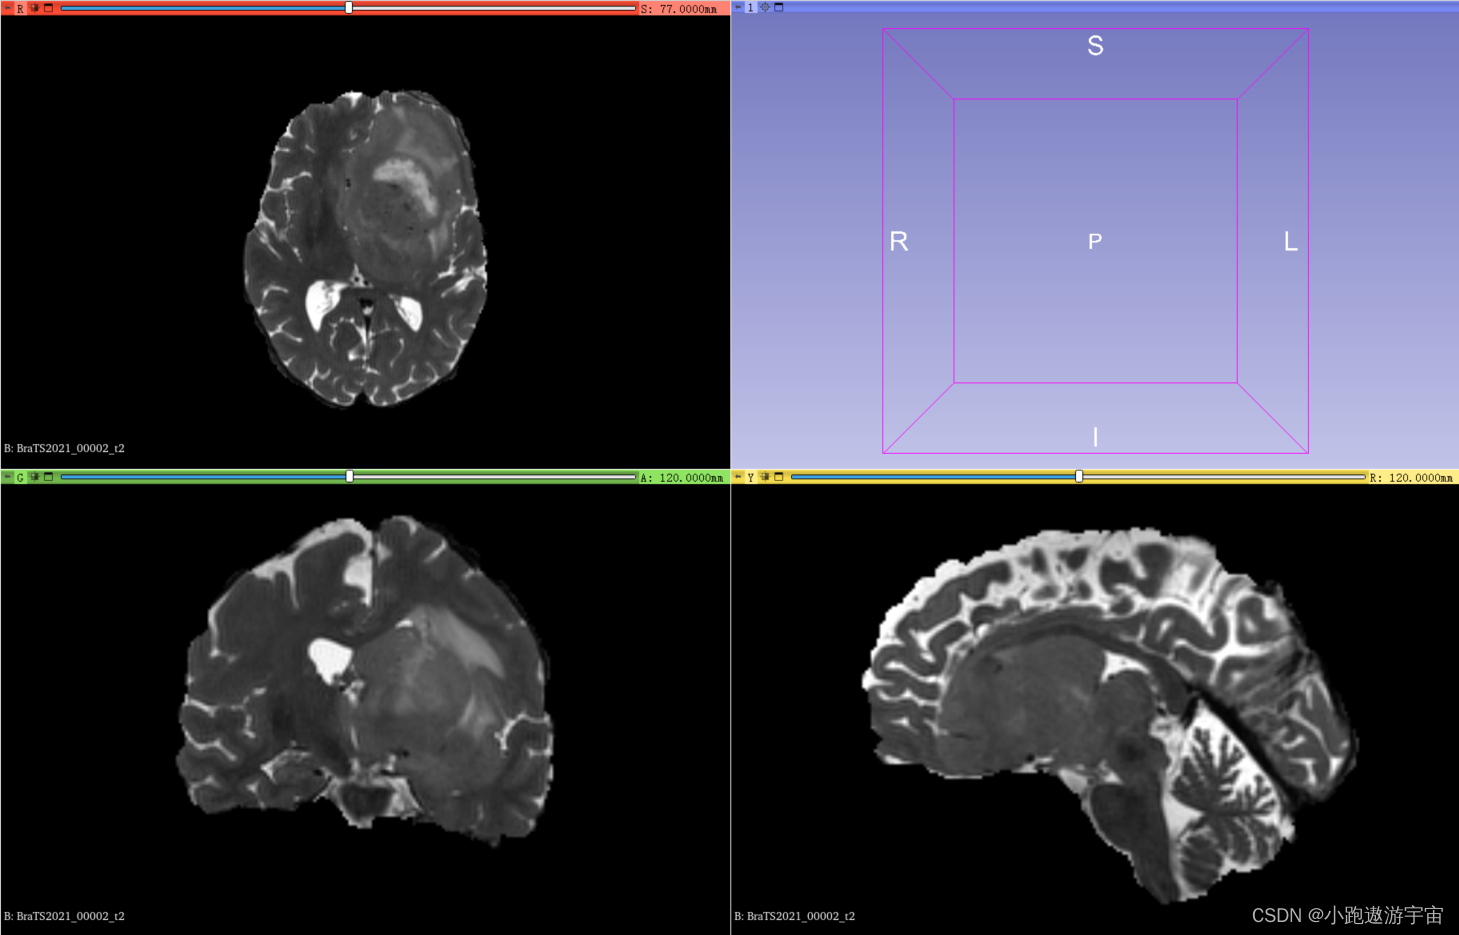

T2加权成像(T2-weighted imaging, T2):这种成像方式通过对人体进行磁共振成像,使用对T2信号敏感的成像方法,呈现出人体组织的水分布情况。T2序列主要用于显示病变的水肿或液体。

BraTS2021_00002_t2.nii.gz